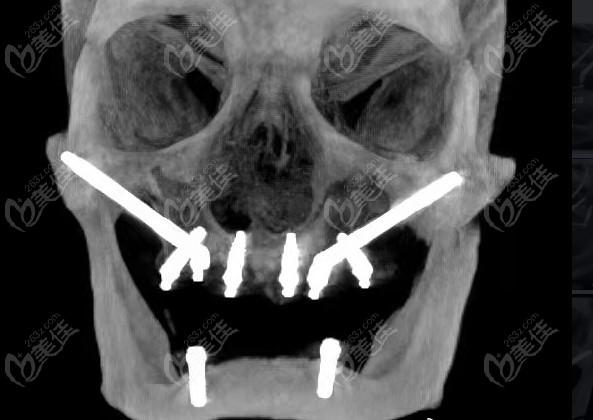

种植牙穿颧有没有后遗症?这是许多需要进行种植牙手术的人们所担心的问题。穿颧骨种植牙是一种比较复杂的手术,需要在颧骨(颧弓)骨质中进行植骨,以提供足够的支撑力。在穿颧骨种植牙的过程中,患者和医生都需要注意一些风险和注意事项。本文将从几个方面对种植牙穿颧有没有后遗症进行详细的阐述,帮助读者更好地了解穿颧骨种植牙手术。

穿颧骨种植牙是一种相对比较安全可靠的牙齿修复方式,具有以下优点:

穿颧骨种植牙虽然具有许多优点,但是也存在一定的风险。在进行穿颧骨种植牙手术前,医生需要对患者进行全面的检查,以确定患者是否适合进行此项手术。以下是穿颧骨种植牙的风险和注意事项: